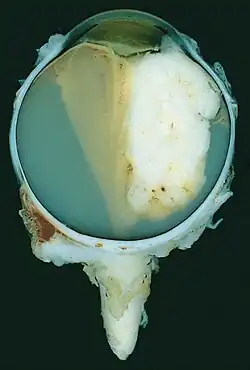

| A pathology specimen of a retinoblastoma tumor from an enucleated eye of a 3-year-old female | |

Gross and microscopic appearances of retinoblastoma are identical in both hereditary and sporadic types. Macroscopically, viable tumor cells are found near blood vessels, while zones of necrosis are found in relatively avascular areas. Microscopically, both undifferentiated and differentiated elements may be present. Undifferentiated elements appear as collections of small, round cells with hyperchromatic nuclei; differentiated elements include Flexner-Wintersteiner rosettes, Homer Wright rosettes,[31] and fleurettes from photoreceptor differentiation.[32]